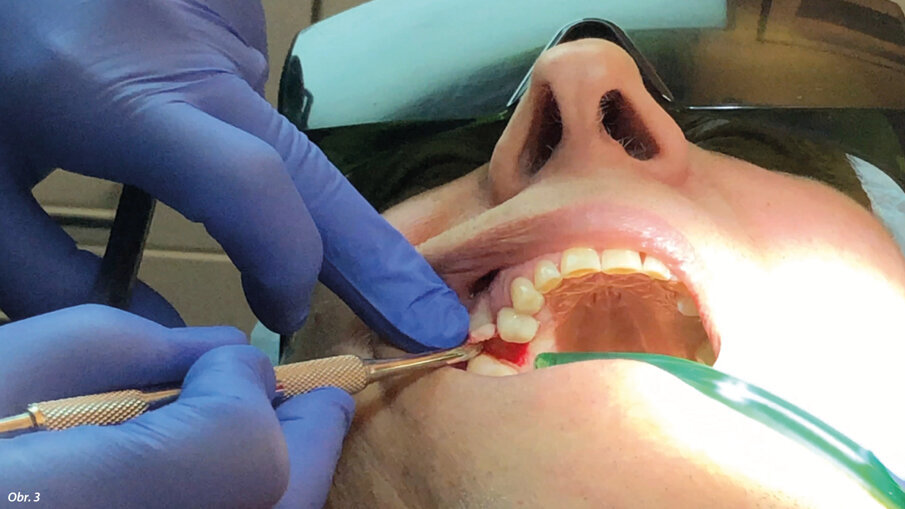

67letý pacient, nekuřák, bez jakýchkoli systémových onemocnění, byl vyšetřen pomocí CBCT (PaX-i3D Smart, Vatech) za účelem vyhodnocení operované oblasti, objemu kosti a hustoty kosti v bezzubé oblasti zubu 15 (obr. 1). Před chirurgickým zákrokem obdržel pacient veškeré informace týkající se ošetření a prostřednictvím individuálního informovaného souhlasu byl informován o možných alternativách ošetření. Osa zavedeného implantátu byla naplánována s ohledem na dosažení nejlepšího funkčního výsledku náhrady. Pro intraorální oporu Er:YAG násadce ve správné poloze odpovídající ose zavádění implantátu byl vytvořen individuální držák z dentální pryskyřice. Byla aplikována lokální anestezie ve formě artikainu (1 : 100 000). Pomocí Nd:YAG laseru (vlnová délka 1 064 nm; vlákno o průměru 200 μm; MSP: 3 W, 70 Hz; LightWalker AT, Fotona) byl na palatinální paramediální linii proveden mukoperiostální řez a současně s ním i dva meziální a distální uvolňující řezy nezasahující papilu (obr. 2). Přístupový lalok pak byl odklopen Prichardovým elevátorem (obr. 3).

Odklopení laloku bylo provedeno Prichardovým elevátorem.